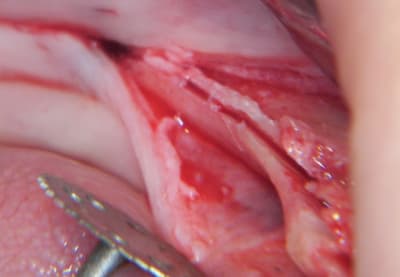

ou bien une comme ça:

--

xbk

"Si tous ceux qui croient avoir raison n'avaient pas tort, la vérité ne serait pas loin" Dac Pierre